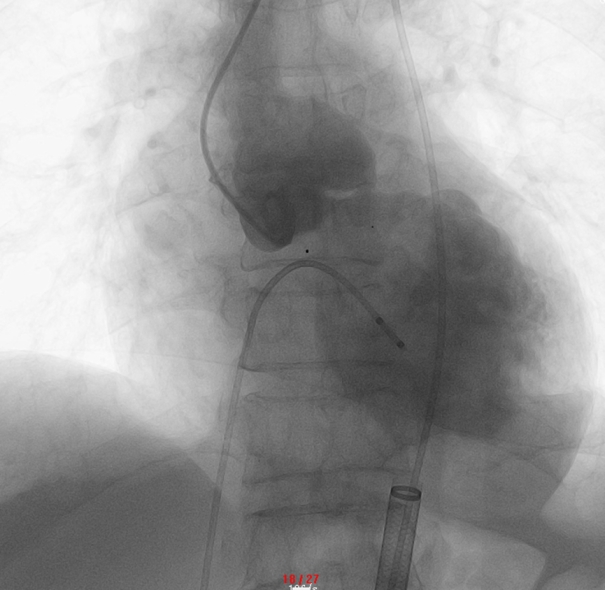

▲ 主动脉根部造影:瓣叶脱垂,可见主动脉瓣重度返流